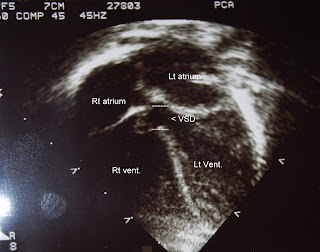

So here's a little lesson on the heart and a VSD. Your heart has 4 chambers, the 2 top ones, the atriums and the 2 lower ones, the ventricles. There is a "wall" that separates the ventricles from one another called, the ventricular septum, this is were her hole is. The lower half of the septum is very muscular and if a hole occurs here it usually closes on its own or a catheterization procedure can take care of it. Unfortunately Jordan's defect is in the upper membranous portion of the septum. These can close on their own when small but Jordan's, being 7mm, is considered on the large side, this means big time open heart surgery is in the future. The problem this hole causes is the oxygen rich blood from the left ventricle gets sucked into the right ventricle instead of getting pumped to the body. The oxygen rich blood then mixes with the oxygen poor blood of the right ventricle and gets sent to the lungs, again. This causes an over abundance of blood to go to the lungs which causes rapid breathing, increased heart rate and a whole slew of other problems. Surgery needs to be performed before certain symptoms become too prevalent in order to protect the lungs and heart from permanent damage.

A picture of Jordan's VSD